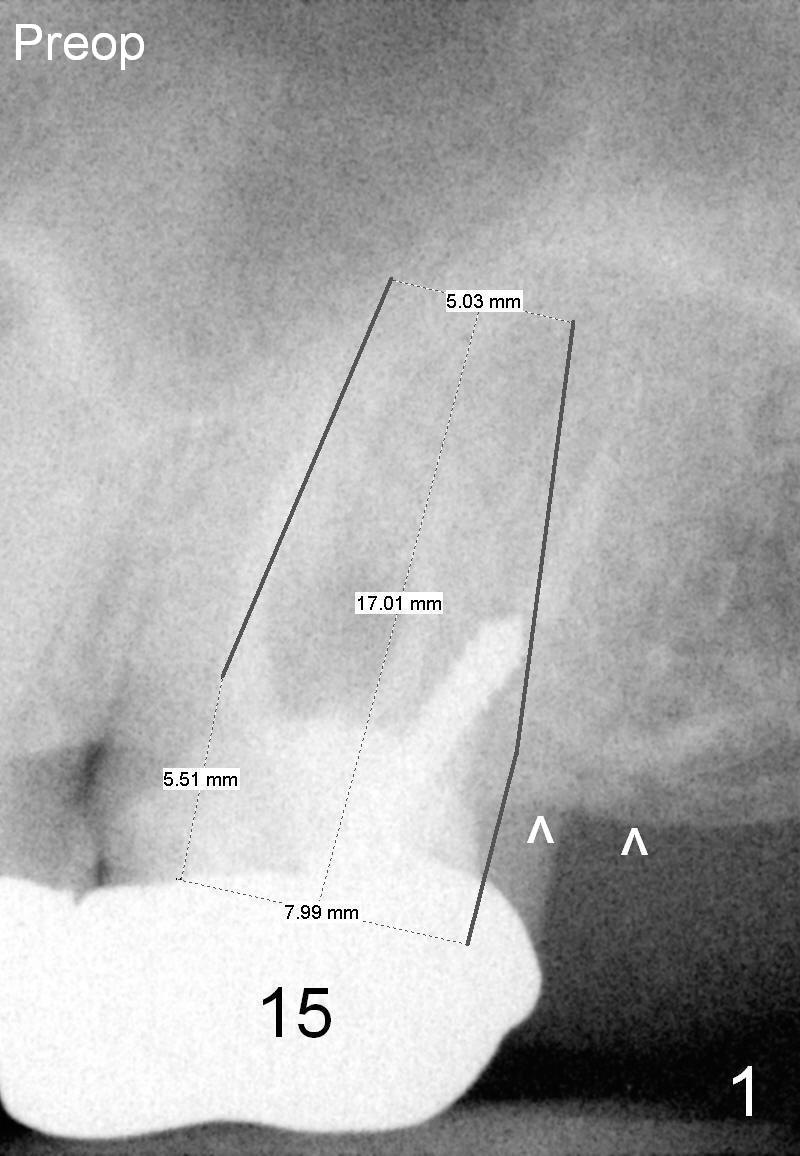

The tooth #15 is going to be extracted due to repeated furcal infection; the distal crest appears to be flat (Fig.1 ^). Two and a half months post extraction, a 6x17 mm tap is placed (Fig.2) prior to placement of a 8x14 mm tissue-level implant (Fig.3). It is apparent that the crest bone has started bone loss (^).